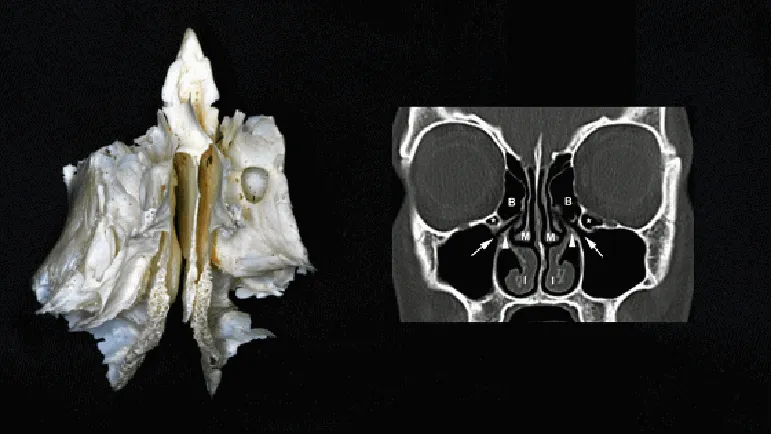

鼻窦作为鼻腔周围颅骨内的含气空腔,共4对(上颌窦、额窦、筛窦和蝶窦)。其中筛窦因与眼眶毗邻而具有特殊重要性。视神经、眼动脉等重要结构通过视神经管和眶上裂,与筛窦解剖关系密切。筛骨作为颅底中最具核心地位的骨骼,包含多个孔洞结构。筛骨迷路位于筛骨两侧,其外表面构成眼眶内侧壁(即眶板或筛骨纸样板),该区域包含多个小房即筛窦。

筛窦与眼眶之间仅以极薄骨板分隔,其中纸样板最为薄弱,眼眶骨折时易发生于此处。筛窦的解剖变异(如纸样板变薄或筛窦气房与眼眶距离过近)会增加手术中眼眶并发症的风险。外科医生需充分认识这些解剖变异,并在手术操作中保持警惕。